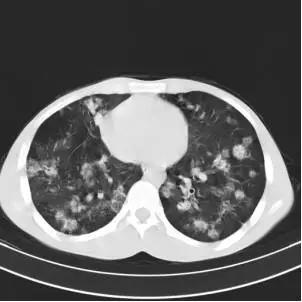

肺结核ct影像表现图解,正常肺与肺结核ct图片

正常肺与肺结核ct图片

CT肺结核图片

肺结核CT

肺结核ct影像图片

肺结核ct影像

肺结核的ct图片